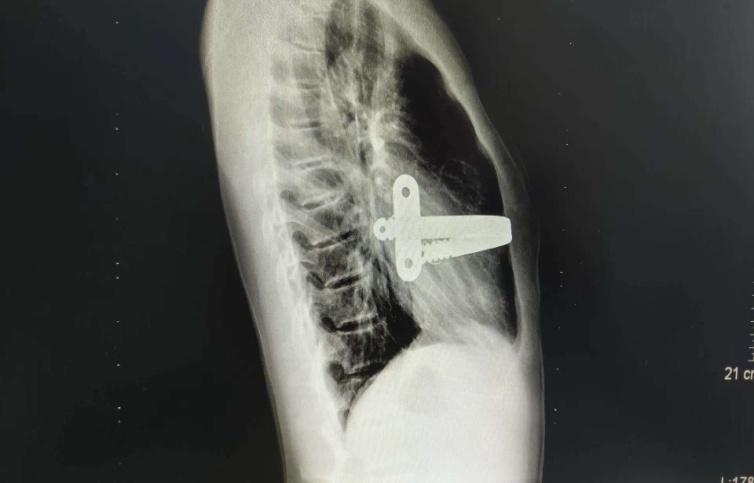

图八 漏斗胸NUSS微创矫正术